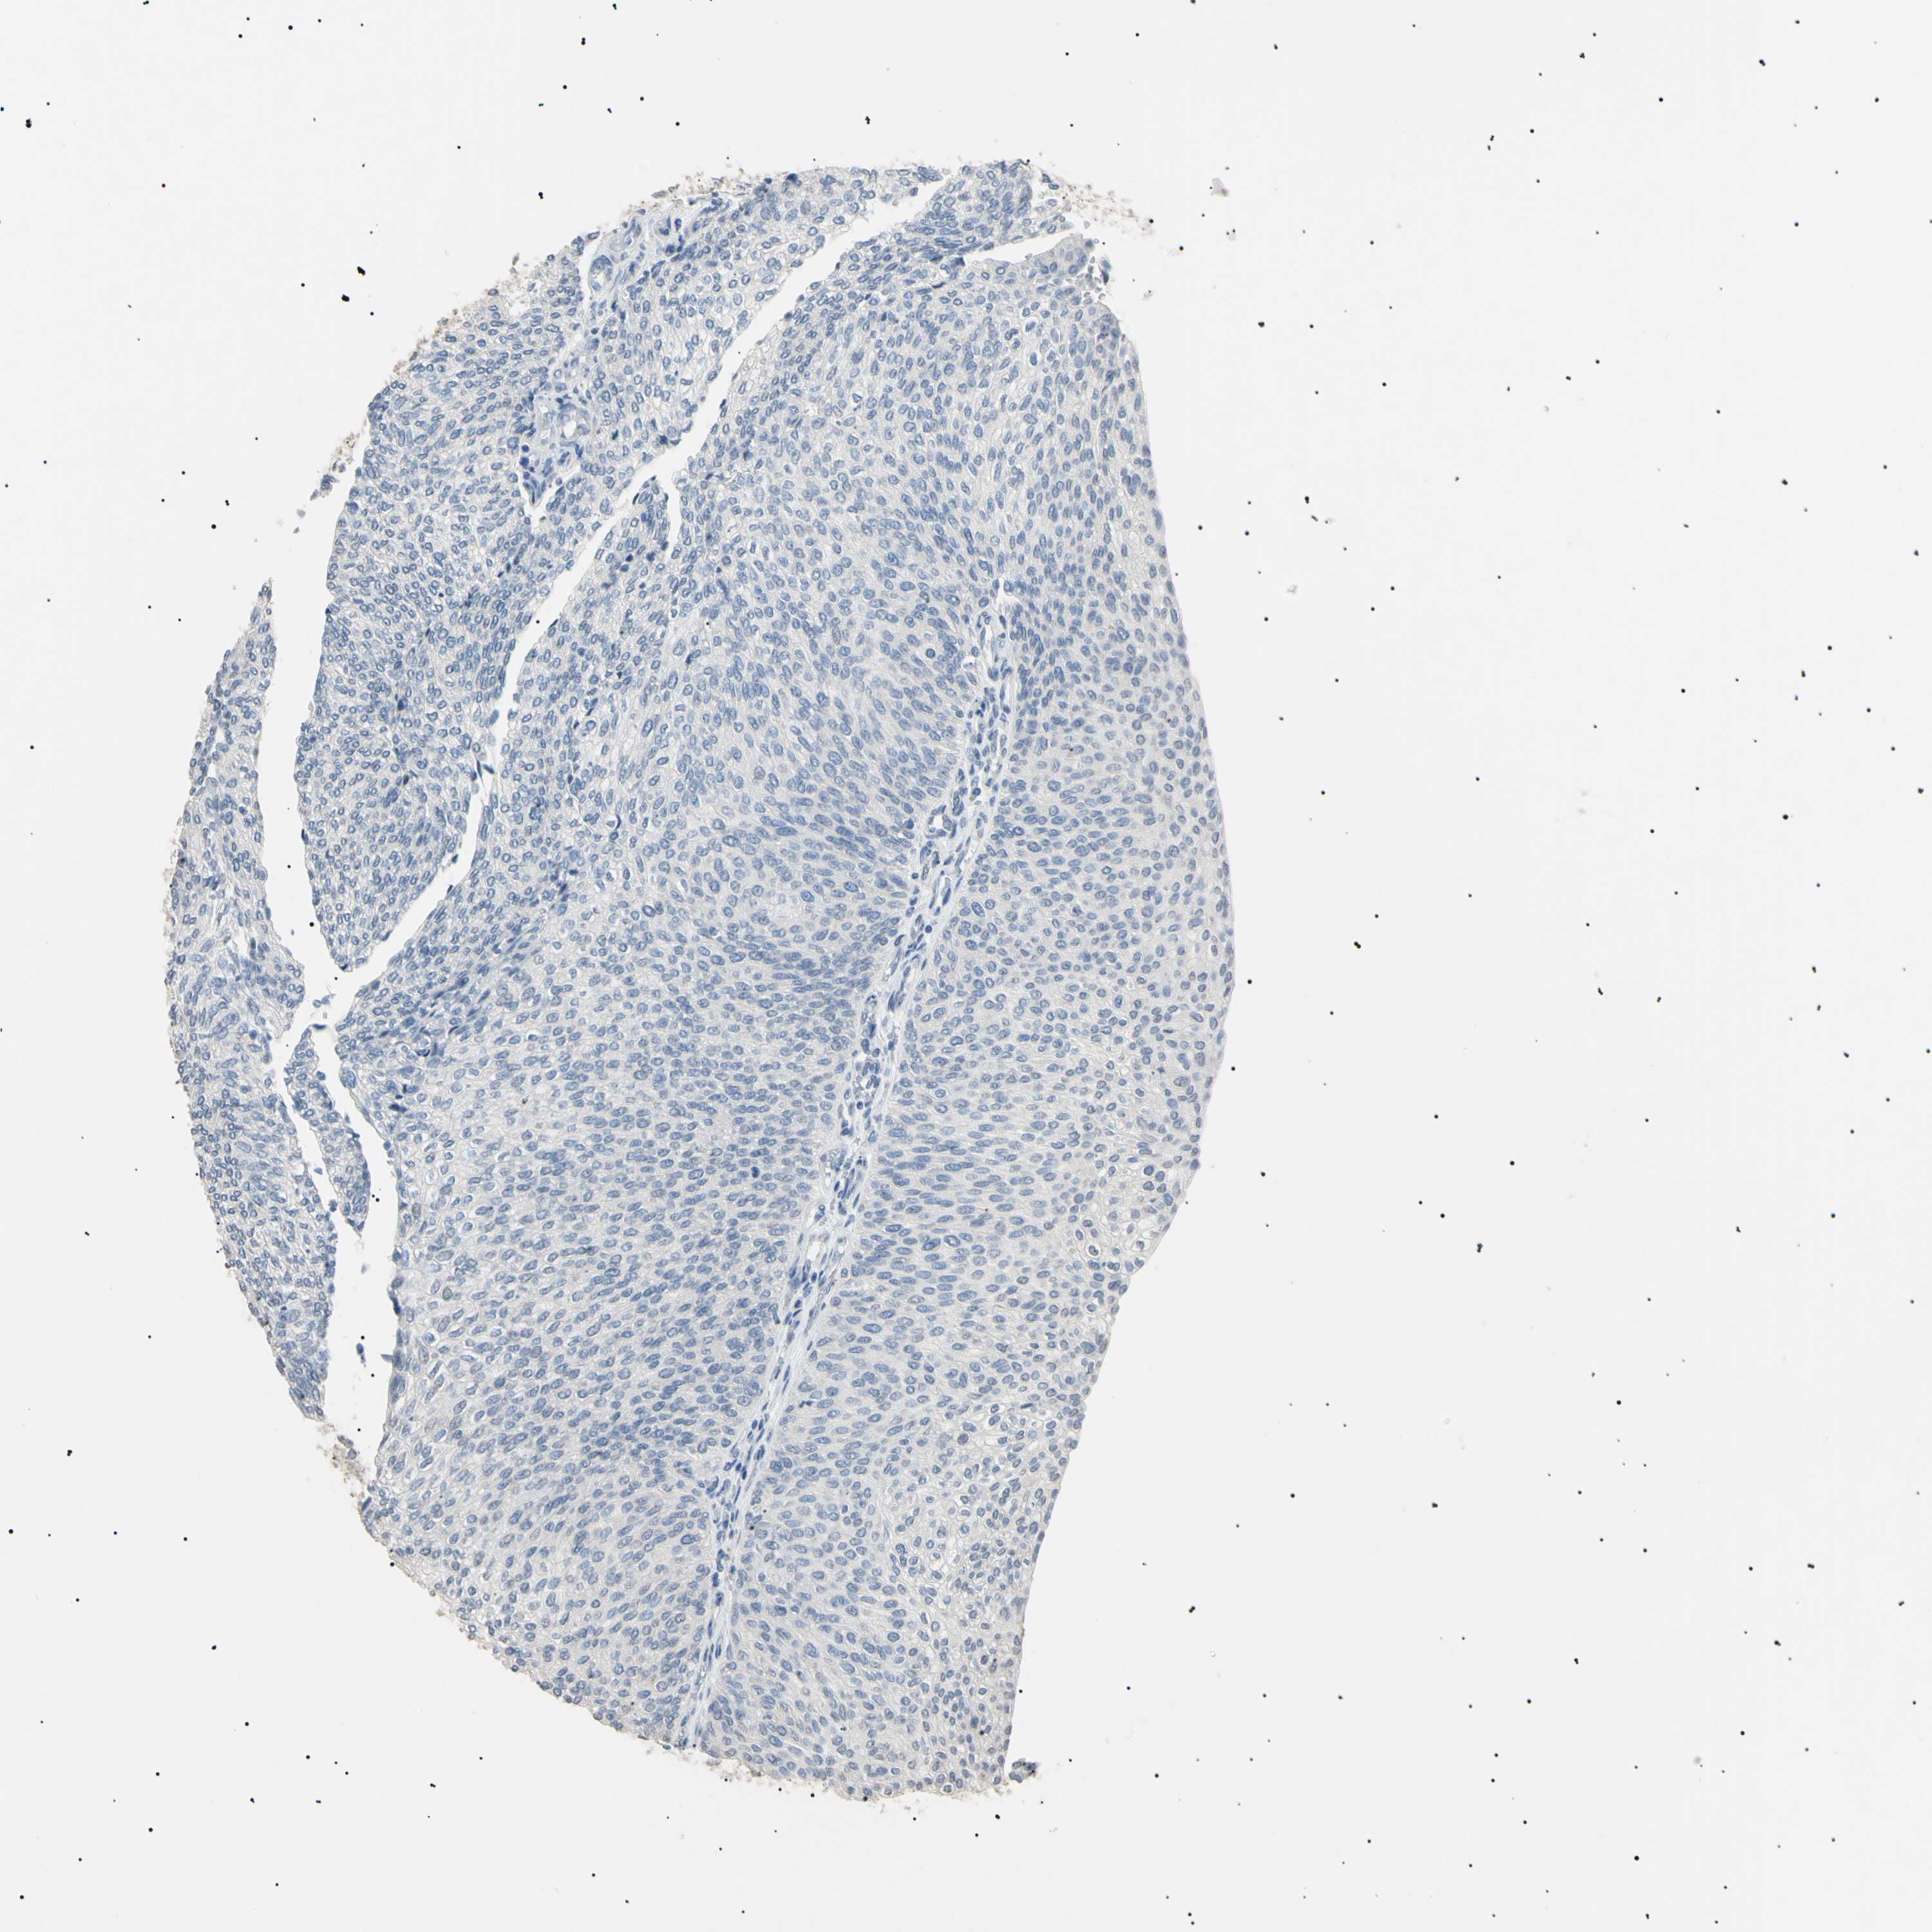

UROTHELIAL CANCER - Protein expressioni

A mouse-over function shows sample information and annotation data. Click on an image to view it in a full screen mode. Samples can be filtered based on level of antibody staining by selecting one or several of the following categories: high, medium, low and not detected. The assay and annotation is described here.

Note that samples used for immunohistochemistry by the Human Protein Atlas do not correspond to samples in the TCGA dataset.

Antibody stainingi

Antibody staining in the annotated cell types in the current human tissue is reported as not detected, low, medium, or high, based on conventional immunohistochemistry profiling in selected tissues. This score is based on the combination of the staining intensity and fraction of stained cells.

Each image is clickable and will lead to virtual microscopy that enables deeper exploration of all samples and also displays staining intensity scores, fraction scores and subcellular localization as well as patient and tissue information for each sample.

Antibody HPA038925

Antibody HPA038934

Antibody CAB000042

Antibody CAB010884

Staining

High

Medium

Low

Not detected

Intensity

Strong

Moderate

Weak

Negative

Quantity

>75%

75%-25%

<25%

None

Location

Nuclear

Cytoplasmic/membranous

Cytoplasmic/membranous,nuclear

Urothelial carcinoma, High grade

Urothelial carcinoma, Low grade

Adenocarcinoma, NOS